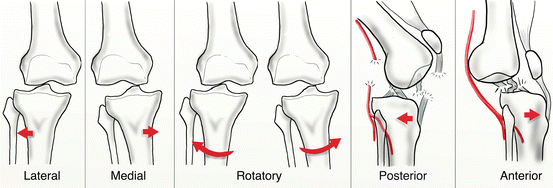

Subluxatia si luxatia articulara Cand soldul - luxat POST